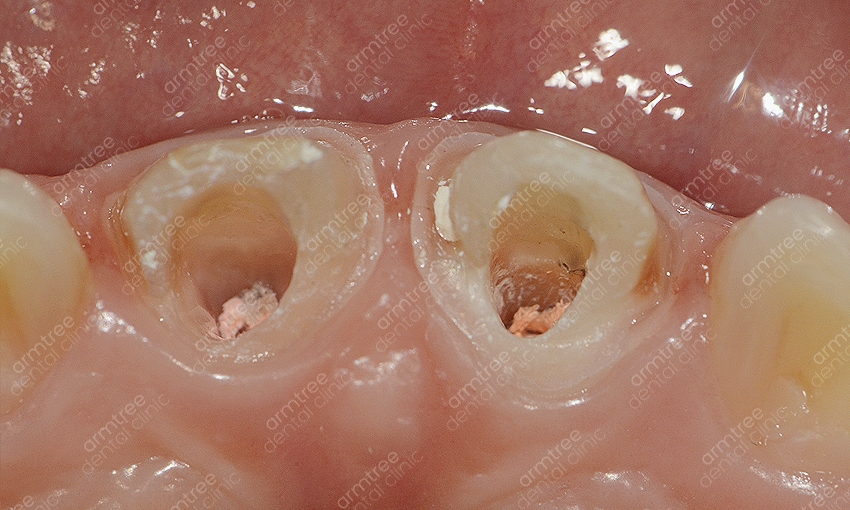

신논현역 치과 아름드리치과에서 실활치미백을 진행하는 과정을 알려드릴께요. 먼저 치아 내부의 신경과 혈관 등이 괴사한 경우라면 신경치료를 우선적으로 진행해요. 신경치료를 마무리 한 후 입술보호제를 꼼꼼히 발라주고 신경 쪽을 막은 뒤 미백제를 투여하는 과정을 진행해요. 충전된 미백제 입구를 막고 상태를 지켜본 뒤 간격을 두고 미백약제를 교체하여 몇 번의 과정을 반복해주어요. 물론 개인차가 존재하지만 대략 2-3회 정도 반복 과정을 한 뒤 미백이 완료되면 입구를 레진으로 수복하여 마무리를 해요. 치아미백을 하시고 난 후 외관상으로 다른 부작용은 없으나 간혹 약간의 시림증상이 발생할 수 있는데요. 하지만 일정 시간이 지나면 곧 괜찮아 지며 변색의 정도가 심해 미백으로 개선이 어려울 시 라미네이트도 대안이 될 수 있다는 걸 알아두세요. 앞니변색으로 인하여 미백을 진행할 경우 하얀 치아로 개선하는 것도 중요하겠지만 다른 치아와의 컬러 밸런스가 필요해요. 하나만 홀로 하얗다면 검거나 누런 것과 비슷하게 심미적으론 좋지 않기 때문에 색상 조절을 잘 해줄 수 있는 전문적인 의료기관을 선택해야 하겠어요.